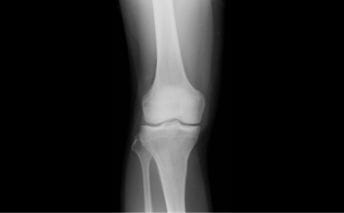

検査:レントゲン

CR(コンピューターX線撮影)は、X線を使って人間の透過像を作ります。各組織の1方向からの撮影のため、CT検査より短時間かつ低被曝での検査が可能です。

- 特長

- 短時間・低被曝

CT(コンピューターX線撮影)

CTはX線を使った人間の身体の透視画像を作ります。カメラが身体の周りをグルグル回り、輪切りの画像を何枚も撮り、単純な断層画像だけでなく、それらをつなぎ合わせて立体的な画像の作成もできます。

- X線吸収差の大きい骨や肺の描出に優れている